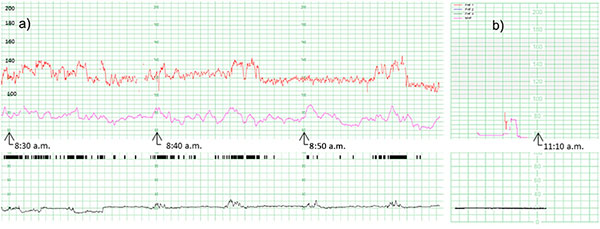

4. Основні параметри оцінки КТГ

- Базальна частота серця плода (110–160 ударів за хвилину в нормі).

- Варіабельність серцевого ритму (незначні коливання частоти).

- Наявність прискорень (ускорення серцебиття) — хороший знак.

- Відсутність чи наявність уповільнень серцебиття (децелерацій), які можуть свідчити про гіпоксію.